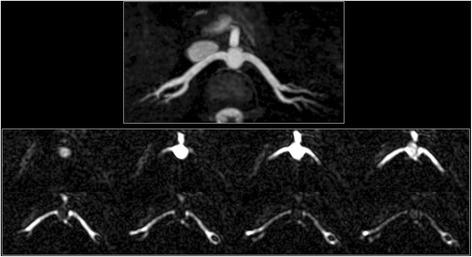

The study was IRB-approved and subjects provided consent. Breath-hold cine FISS and bSSFP were acquired using similar imaging parameters. There was no significant difference in biplane left ventricular ejection fraction or cardiac image quality between the two techniques. Compared with cine bSSFP, cine FISS demonstrated a marked decrease in fat signal which improved conspicuity of the coronary arteries, while suppression of through-plane flow artifact on thin-slice cine FISS images improved visualization of the aortic valve. Banding artifacts in the subcutaneous tissues were reduced. In healthy subjects, dynamic flow patterns were well visualized in the aorta, coronary and renal arteries using cine FISS ASL, even when the slice was substantially thicker than the vessel diameter.

Cine FISS demonstrates several benefits for cardiovascular imaging compared with cine bSSFP, including better suppression of fat signal and reduced artifacts from through-plane flow and off-resonance effects. The main drawback is a slight (~ 20%) decrease in temporal resolution. In addition, preliminary results suggest that cine FISS ASL provides a potential alternative to phase contrast techniques for in-plane flow quantification, while enabling an efficient, visually-appealing, semi-projective display of blood flow patterns throughout the course of an artery and its branches.

该研究获得了机构审查委员会的批准,受试者提供了同意。使用类似的成像参数获取屏气电影 FISS 和 bSSFP。两种技术之间的双平面左心室射血分数或心脏图像质量没有显著差异。与电影 bSSFP 相比,电影 FISS 显著降低了脂肪信号,提高了冠状动脉的显影,而在薄层电影 FISS 图像上抑制了平面内流动伪影,改善了主动脉瓣的可视化。皮下组织中的带状伪影减少。在健康受试者中,使用电影 FISS ASL 可以很好地可视化主动脉、冠状动脉和肾动脉中的动态流动模式,即使切片厚度明显大于血管直径。

与电影 bSSFP 相比,电影 FISS 显示出对心血管成像的多种优势,包括更好地抑制脂肪信号和减少平面内流动和离共振效应产生的伪影。主要缺点是时间分辨率略有下降(约 20%)。此外,初步结果表明,电影 FISS ASL 为平面内流量定量提供了一种替代相位对比技术的潜在方法,同时能够有效地、以吸引人的半投影方式显示整个动脉及其分支的血流模式。